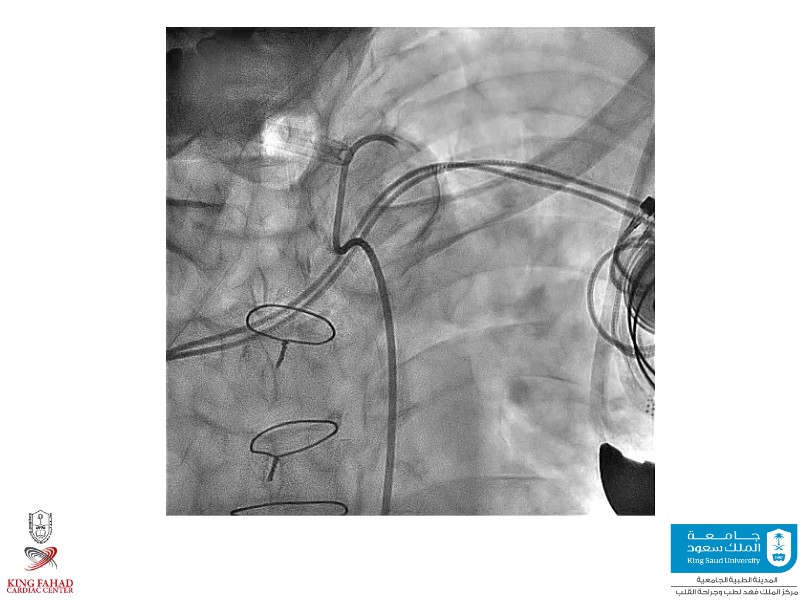

Second valve strategies with SAPIEN 3 Ultra RESILIA

This session helps you anticipate and address complex scenarios such as mitral valve-in-valve, TAV-in-SAV, and valve-in-valve-in-valve procedures. Learn from expert case discussions that explore procedural strategies, technical challenges, and best practices to optimize outcomes in redo structural heart interventions.